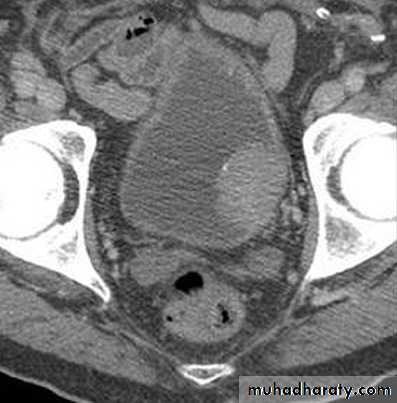

Ct enhanced

Big simple renal cyst(non enhancing mass homogenous) treatment is conservative or drainge if symptomaticWhat's the Diagnosis?